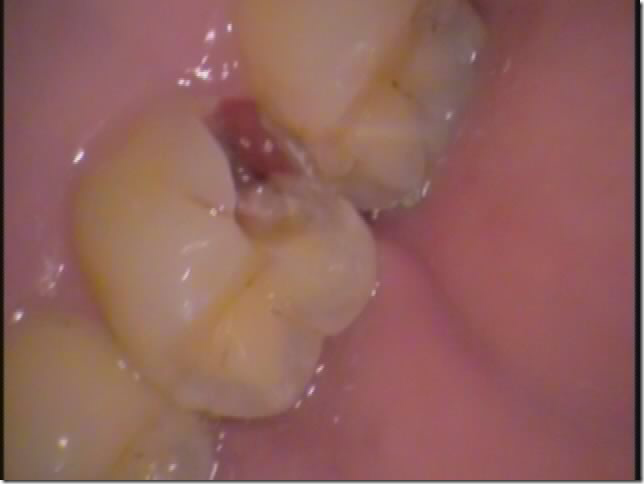

小中学生のフッ素塗布